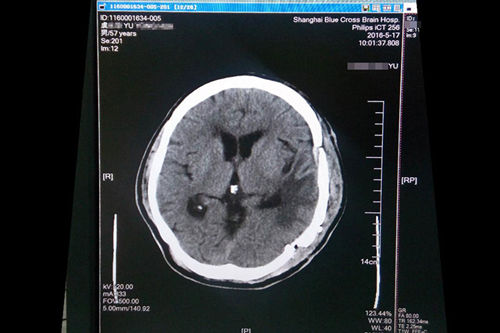

2016年4月,浙江宁波人,57岁的虞文军(化名)因巨大脑肿瘤(8*6cm) 前来上海蓝十字脑科医院就诊。经包括沈建康教授在内的专家会诊后,考虑到患者脑肿瘤巨大、肿瘤周边血供丰富,手术指征明确,常规手术切除恐出血过多,增加手术风险,决定术前先为虞文军行“超选择性全脑血管造影术+脑膜瘤供血动脉栓塞术”,对肿瘤供血动脉进行栓塞,减少出血量,再全麻下行“左侧颞底部巨大脑膜瘤切除术”。沈教授已经有十年未见过患者有如此大的肿瘤,患者术后随即恢复清醒,自我感觉头脑较前更清醒,语音、语速恢复较好,不到半个月便已能正常行走,顺利出院。

术后一个月复查CT影像显示恢复良好